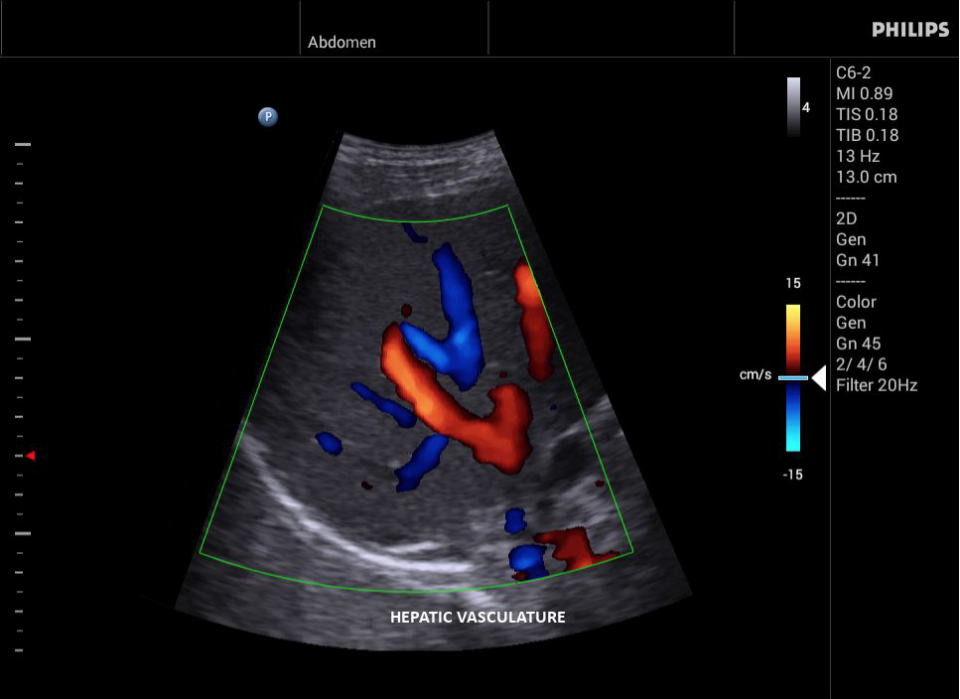

• Конвексный УЗИ датчик Philips С6-2

• Исследования сосудов;

• Цветное допплеровское картирование